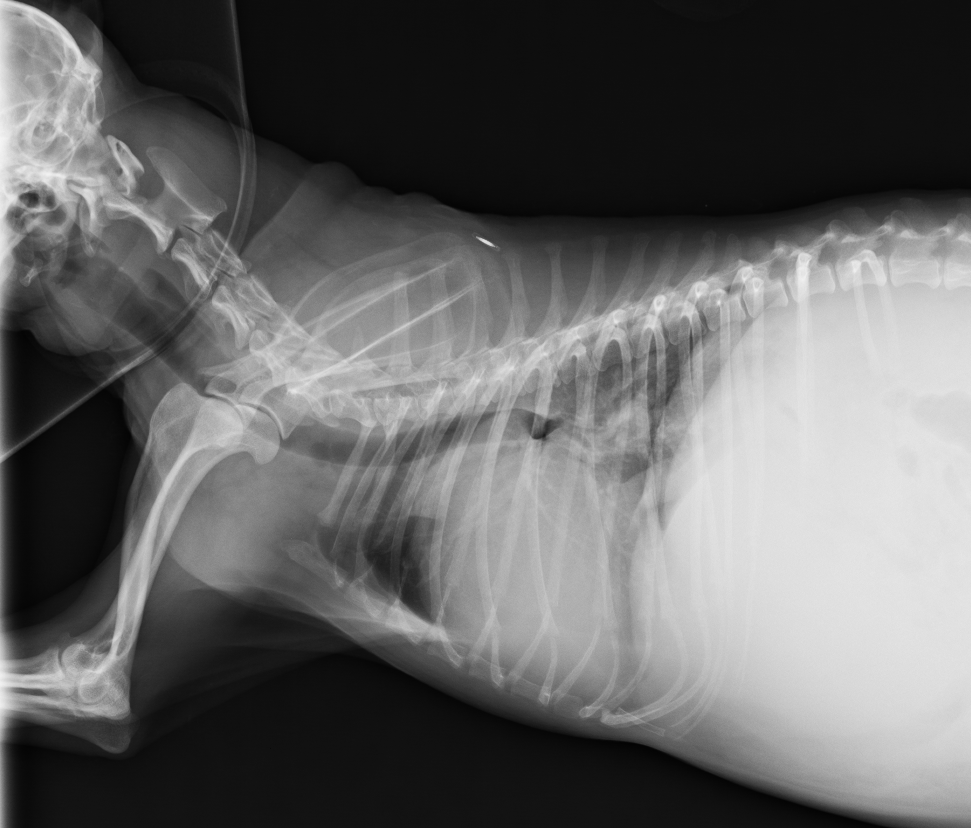

術前胸腔X光:心臟肥大,腹部有嚴重腹水